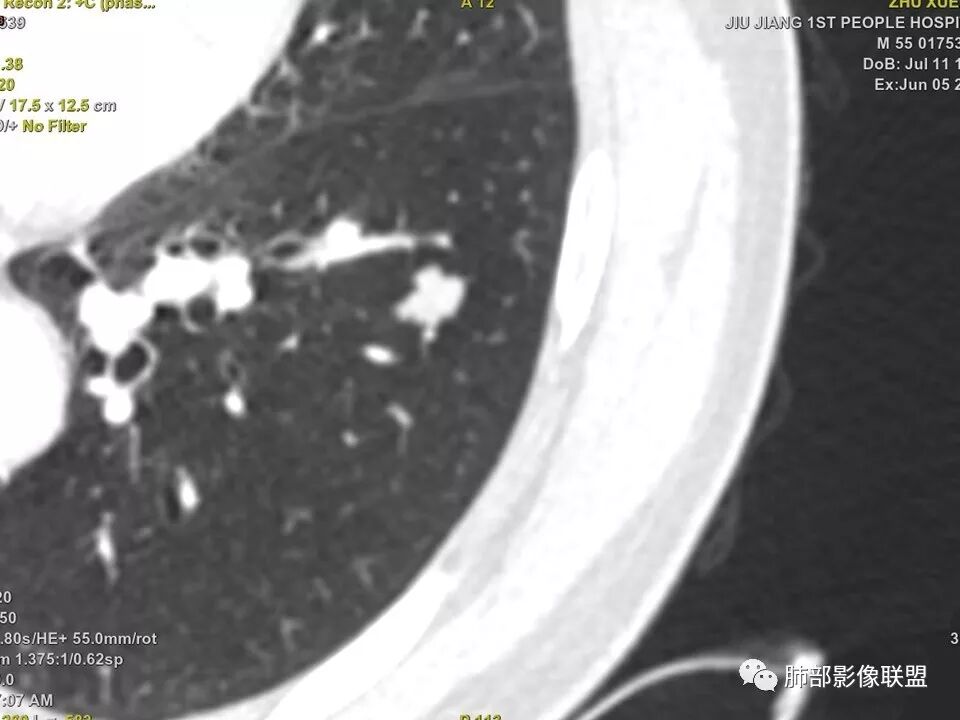

左肺下叶前内基底段结节,轮廓凹凸不平,局部边缘平直,密度不均,近段支气管阻塞,增强前后CT值无明显变化,考虑肉芽肿,结核?腺癌代排

左肺下叶前基底段结节,病灶边缘分叶,边缘平直,u型征,可见气管截断,增强可见病灶边缘血管,平扫ct值低,轻度强化。考虑良性病变。

这个病例要特别关注增强前后ct值

晨读病例,强化值小于20,还是提示良性,感觉支气管截断是坑,所以考虑错构瘤?肺癌待排

边缘平直,主要强化值小于20,说明基本不强化,提示良性

实性结节,以收缩为主,强化弱,支气管截断面呈凹面,浅分叶,肉芽肿性炎

支气管截断,结节轮廓凹凸不平,密度不均,无明显强化,部分边缘呈平直征,考虑结核性肉芽肿,腺癌代排

典型CT特征包括:(1)圆形或椭圆形边界清楚的病灶。(2)大小1~4cm,有轻微分叶改变。(3)较均匀的软组织影,多伴有钙化。(4)无毛刺,卫星灶及肺门或纵隔淋巴结肿大。(5)CT增强扫描无强化或轻度强化,其强化可能与软骨瘤间质中的薄壁血管或周围慢性炎症反应有关。